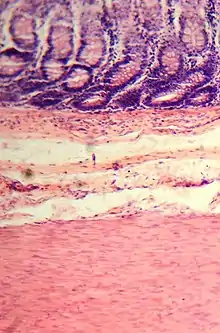

Gros intestin

Le gros intestin est le dernier segment du tube digestif des vertébrés. Il fait suite à l’intestin grêle et s’étend de la valvule iléo-cæcale à l’anus ou au cloaque. En anatomie, il est divisé en deux parties : le côlon et le rectum (plus parfois le canal anal)[1],[2].